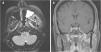

Transpatial skull base lesions involving the infratemporal fossa (ITF) are challenging due to the complex neurovascular structures of the region. Open approaches have traditionally been utilized to access these spaces. We present a 55-year-old woman presented with a mesenchymal mass involving the left ITF and masticator space. A combined endoscopic endonasal transpterygoid approach was performed followed by an endoscopic transoral-transmandibular corridor to access and resect the tumor. The post-operative course was unremarkable with no recurrence during her follow-up. Combined endoscopic approaches for transpatial tumor resection offered sufficient exposure to access safely each space.